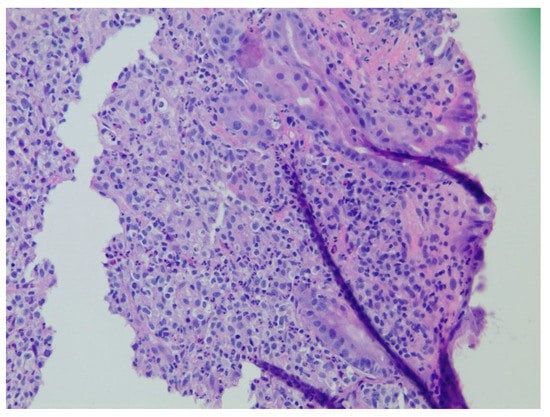

| 1 | F | 66 | Skin | Fundus, cardia, and body | Polypoid lesions with superficial ulcers | Esophagus, duodenum, mediastinum, cervical soft tissue, pancreas | Metastatic malignant melanoma | Radiotherapy and immunotherapy | Comfort care and death 5 days after EGD diagnosis of metastasis |

| 3 | F | 35 | Lung | Fundus | Fungating mass | Esophagus, mediastinum | Large-cell neuroendocrine carcinoma | Chemotherapy-carboplatin/ etoposide | Death 1 month after EGD diagnosis of metastasis |

| 4 | F | 73 | Kidney | Fundus and body | Multiple large friable masses | Liver and lungs | Clear cell renal carcinoma | Nephrectomy, chemotherapy, immunotherapy (Axitinib) | Death 10 days after EGD diagnosis of metastasis |